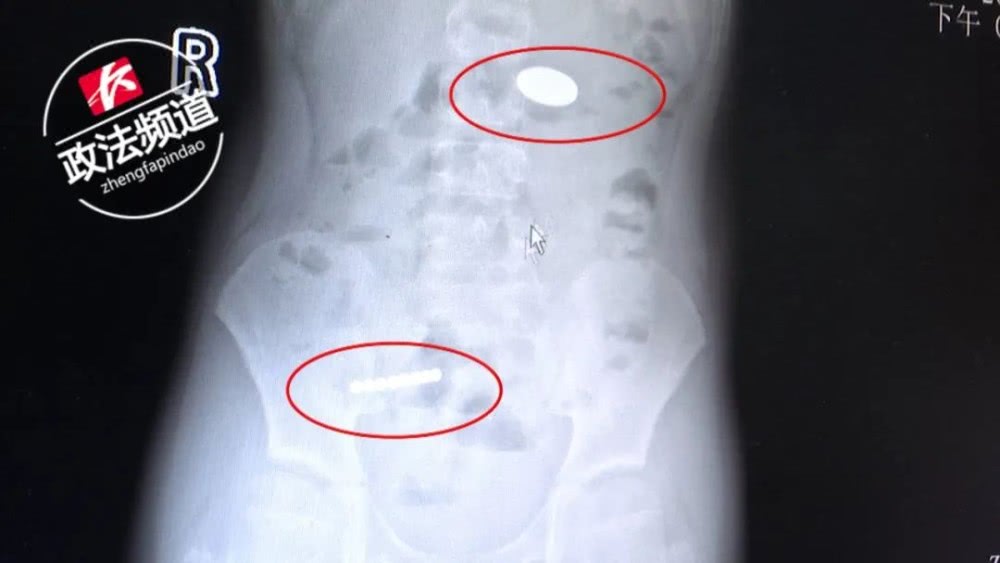

从X线检查结果可以看到

小明右下腹有八颗珠子连在一起,

左上腹还有一枚圆形的物体,好像是硬币。